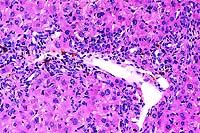

20x

obj

- Case 19-3. Liver. There is diffuse bile duct hyperplasia.

These bile ducts are often surrounded by lymphocytes and plasma

cells. Scattered foci of neutrophils and intrahepatocytic brown

pigment are also present.

- AFIP Diagnosis: Liver: Hyperplasia, biliary and oval

cell, portal and periportal, diffuse, moderate, with multifocal

mild lymphocytic and neutrophilic portal and periportal hepatitis,

individual hepatocyte necrosis, and intracellular brown globular

anisotropic pigment, BALB/cJ-Fech mouse, rodent.